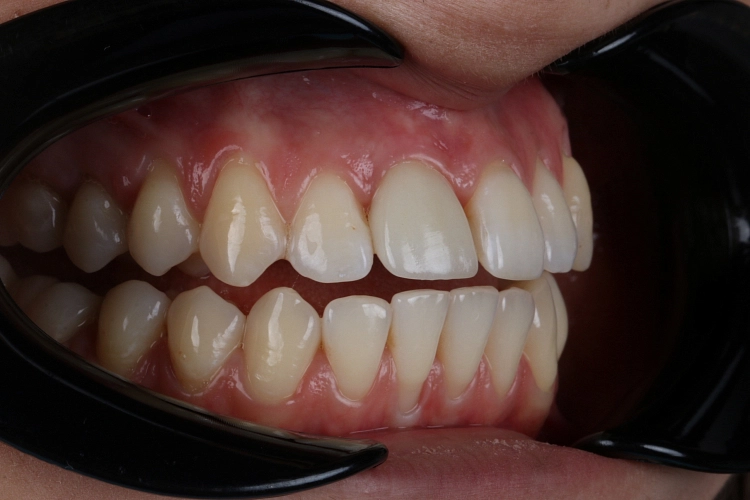

Когда устанавливать имплант после удаления зуба